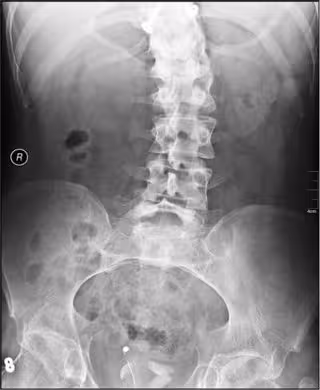

Escoliosis - NEVIT DILMEN - Archivo

La escoliosis es la desviación involuntaria e irreductible de la columna vertebral. En algunos casos aparece en ancianos ('escoliosis del adulto'), pero en la inmensa mayoría lo hace durante la infancia o la adolescencia, etapa en la cual hay dos tipos la 'escoliosis secundaria', debida a malformaciones (como la fusión congénita de algunas vértebras) o asimetrías en la longitud de las piernas; o asociada a algunas enfermedades (como la neurofibromatosis, el síndrome de Marfan o algunas enfermedades neuromusculares).

En esta idiopática, la desviación suele ir progresando hasta que termina el crecimiento y, para seguir su progresión, la curvatura se mide periódicamente (habitualmente una vez al año, o más a menudo si la desviación crece rápidamente) en 'grados Coob', que se calculan mediante unas mediciones realizadas sobre una radiografía de columna.